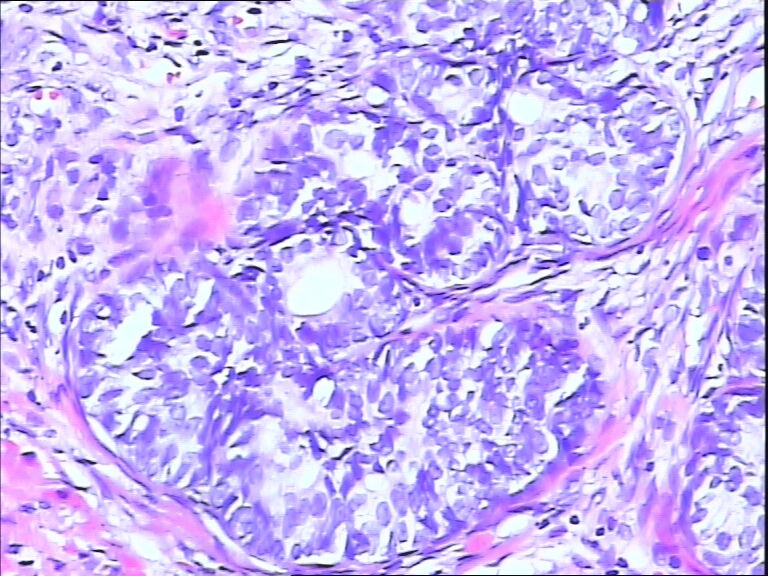

前列腺,请教,急!

图2

前列腺够癌吗?